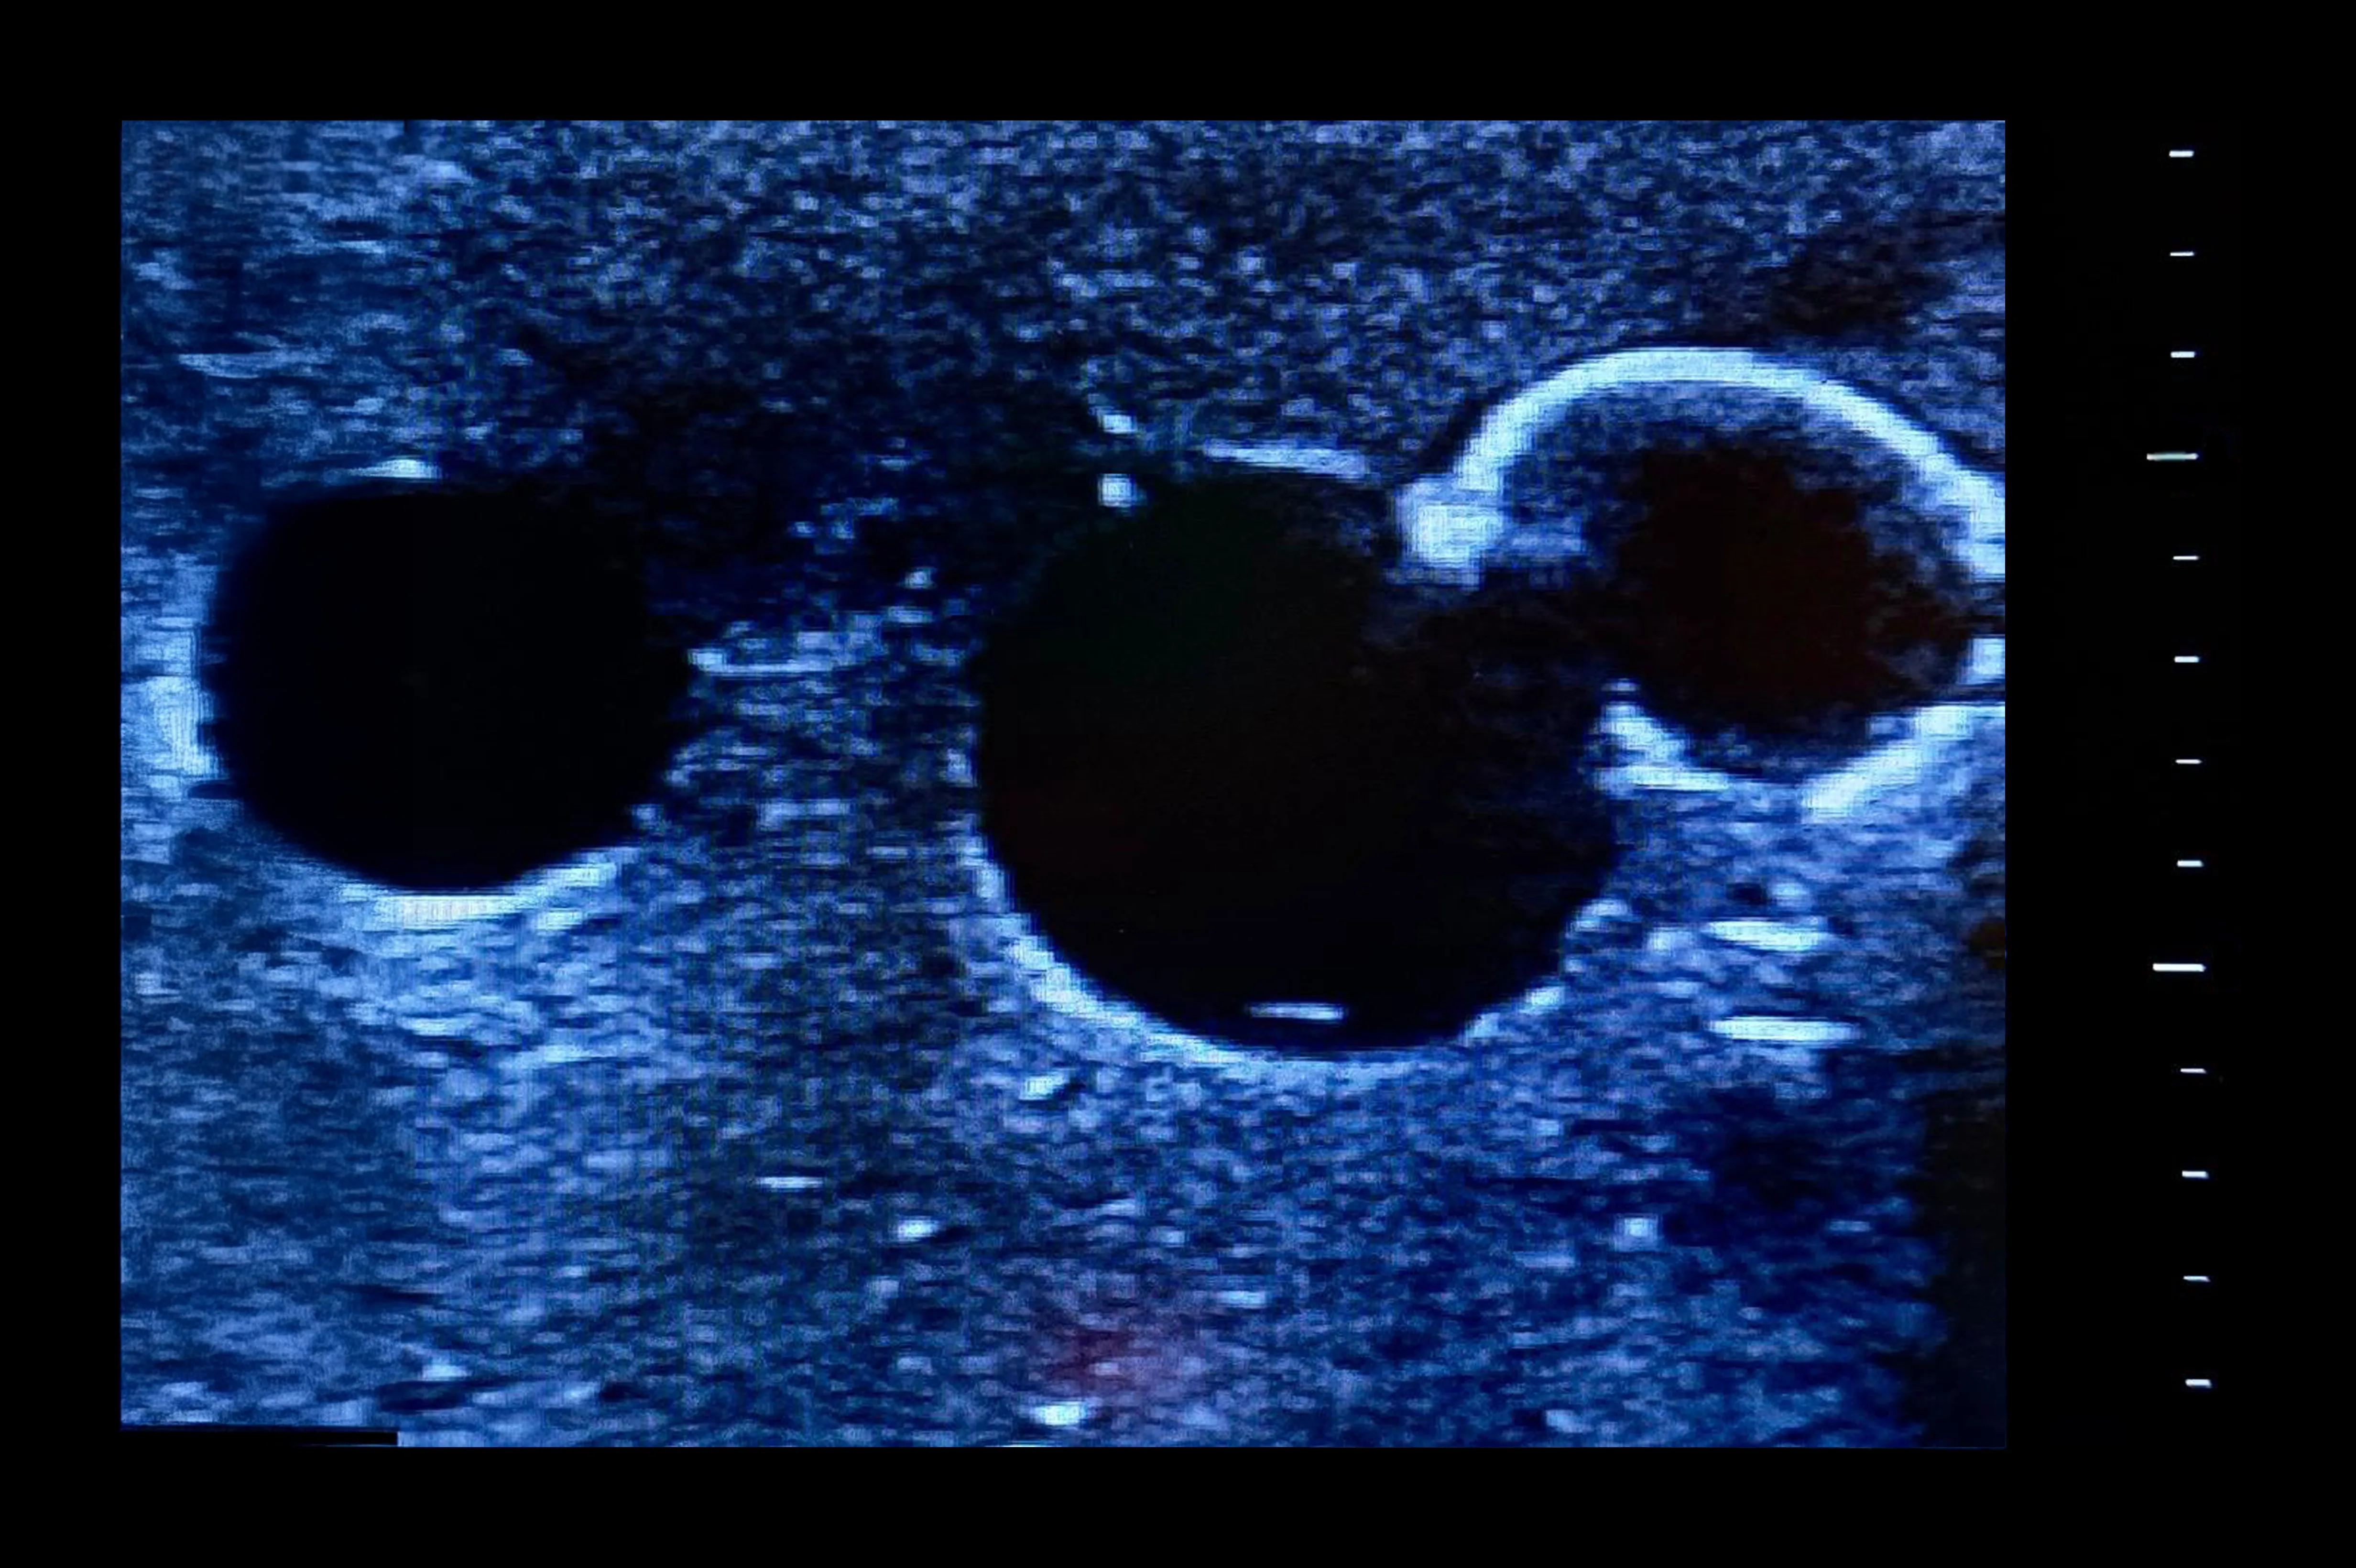

Designed for femoral vascular access training, this simulator features two vertically branched veins (approx. 8 mm diameter, 20 mm deep) with simulated calcifications. Lifelike echogenic material closely mimics human tissue, enabling realistic ultrasound-guided practice, probe control, and anatomy recognition in a safe, repeatable environment for both trainees and experienced clinicians.

- Identification of veins under ultrasound

- For femoral access with two vertically branched blood vessels with simulated calcifications

- Veins of diameters approximately 8 mm, located 20 mm below the surface of the simulator for vascular access

- Tubeless veins occlude when pressed either by hand or ultrasound probe

- Vein occlusion is visible under ultrasound